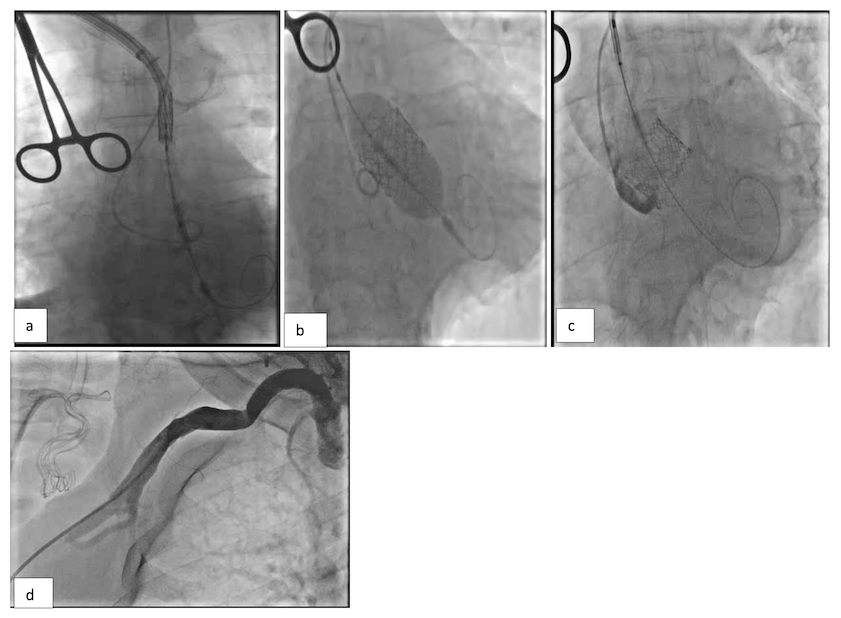

We placed a right radial artery cannula and left radial access for pigtail placement. The right axillary artery was accessed with ultrasound guidance and a 6-French (Fr) sheath was inserted. Two ProGlide sutures were deployed for pre-closure. The 6-Fr sheath was upsized to 11 Fr. The aortic valve was crossed, and a small Safari wire was placed in the left ventricle (LV). A 16-Fr Edwards eSheath was inserted over the Safari wire and positioned in the innominate artery (Figure 1A). The eSheath was partially withdrawn to create space for valve loading (Figure 1B). Once the valve was across the aortic annulus, the pusher catheter was withdrawn to the upper ascending aorta. The flex wheel of the Commander system was angled close to its maximum and the whole apparatus slowly rotated to align the Safari wire on the greater curvature of the aorta. This brought the S3 Ultra valve perfectly into annular alignment (Figure 1C). The 29 mm S3 Ultra valve was deployed in a good position at the aortic annulus, under rapid pacing through the LV wire,18 with no aortic regurgitation (Figure 1D). Vascular closure of the axillary artery was secured with the two ProGlide sutures. There were no procedural complications, and the patient went home the following day.

An aortogram showed moderate aortic regurgitation, therefore the valve was post-dilated with a further 2 milliliters of contrast. However, the leak persisted and led us to implant an 8 mm AVP 4 device using an AL1 catheter in the left coronary sinus to lie parallel to the frame of the Edwards valve. This device placement (Figure 3D) reduced the leak significantly with simultaneous TAVI and para-valvular leak (PVL) closure.19 The vascular closure was secured with a ProGlide followed by a planned 8-Fr Angio-Seal vascular closure device. There were no procedural complications, and the patient went home the next day.